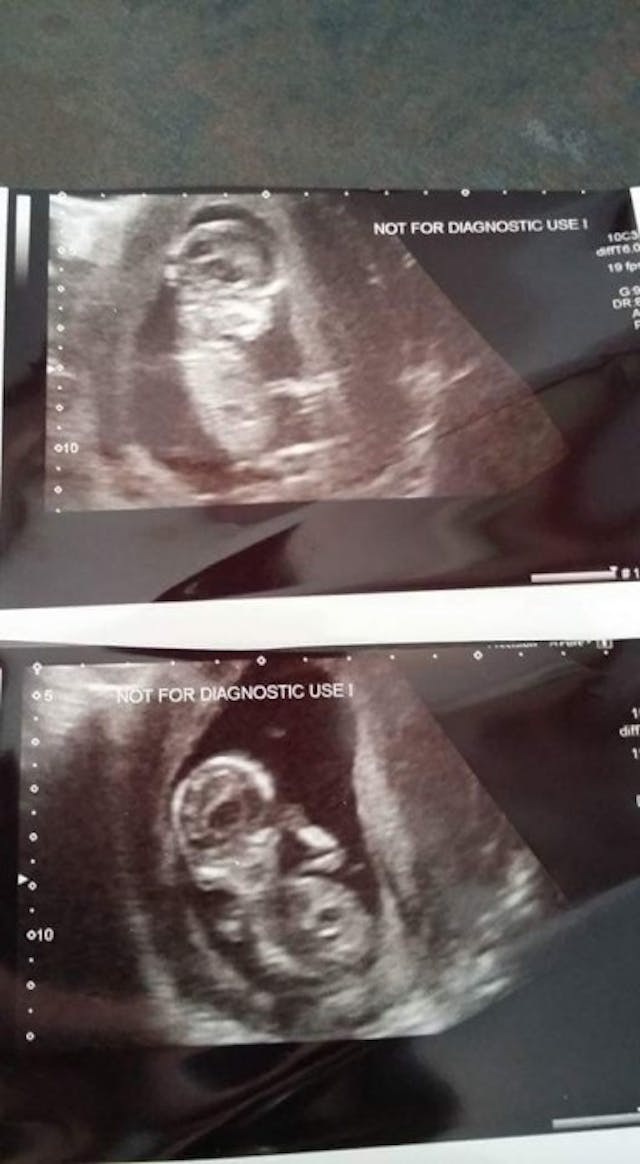

I had a scan around six weeks (as I have a history of recurrent miscarriage) on 21st August, which showed a heartbeat.

I carried on as normal, then I hit 11 weeks gestation and started bleeding on September 16th. I was offered a scan a few days later, which showed my baby alive and seemingly well with no visible sign of where the bleed was coming from.

Then the bleeding got worse, so I was scanned again on the 23rd of September and, again, all looked alright.

Then on October 9th, 2015, the bleeding became heavier and was now passing on to a pad. I was offered another scan and all seemed fine once more, and my baby had been developing as he should have been the entire time.

Here is my son, Phoenix Aesir Mann. Born at 14 weeks and one day on the 11th of October, 2015. My precious sleeping beauty. Look how perfect he is; 10 fingers, 10 toes with nails, a perfect little nose, feet and hands and a beautiful smile. You can see all his veins, too. He was PERFECT. I miss him every day.